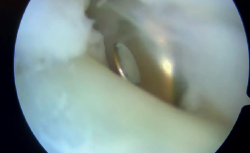

Un año y medio después de la lesión inicial, se realizó una segunda cirugía artroscópica de tobillo. El procedimiento reveló sinovitis anterior de la articulación tibiotalar, que fue desbridada con un sinoviotomo. El CFL estaba intacto, mientras que se observó una rotura parcial menor del ATFL, que se consideró clínicamente sin relevancia. En segundo lugar, se realizó una tenoscopia de la vaina de los tendones peroneos, revelando una rotura de la vaina y el tendón peroneus brevis con integridad del retináculo, visualizándose la fijación proximal del injerto en la fíbula que estaba en contacto con el tendón peroneus brevis, el cual estaba parcialmente desgarrado (Figura 3).

reaca.32385.fs2503006-figura3.png

Figura 3. Tenoscopia de la vaina peronea en el tobillo derecho, donde se observa el dispositivo de fijación proximal dentro de ella, contactando con el tendón del peroneo corto durante las maniobras dinámicas.